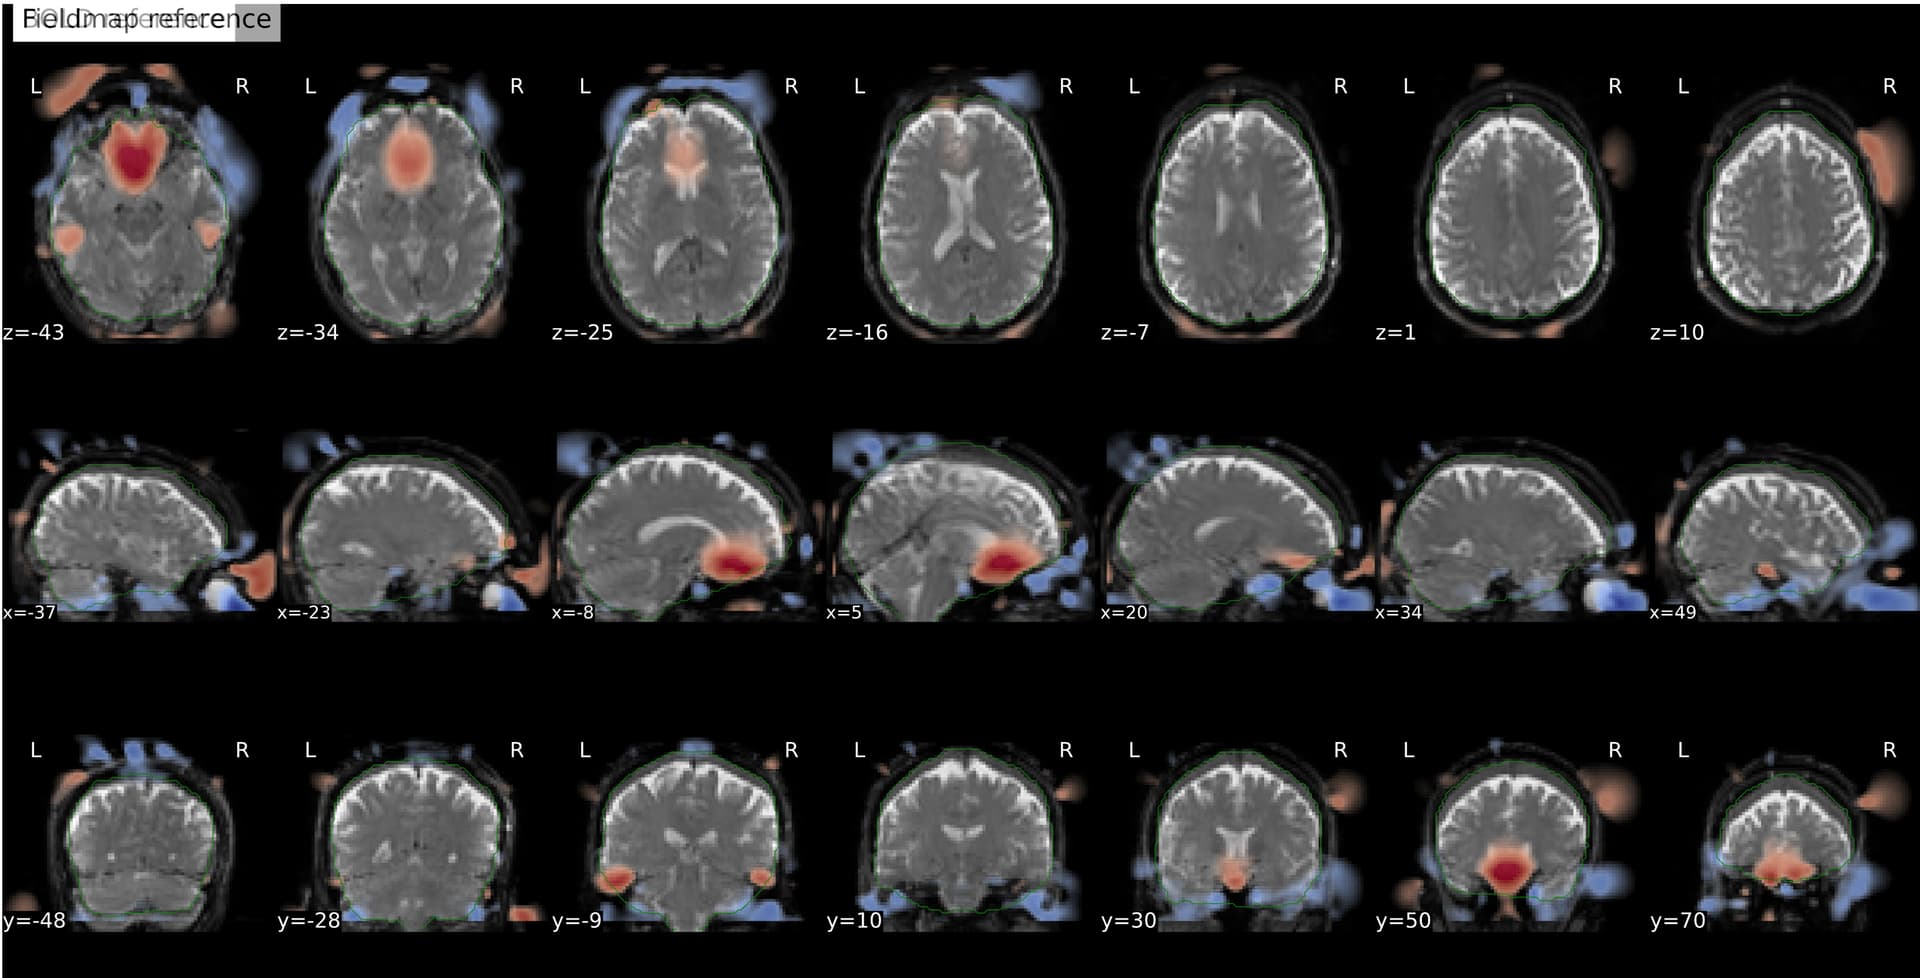

I’m seeing an apparent misalignment in the fmapCoreg reportlet for a PEPOLAR (SE-EPI AP/PA) distortion-correction workflow

- Raw AP/PA fieldmaps and raw BOLD data are perfectly aligned in native space.

Another example: